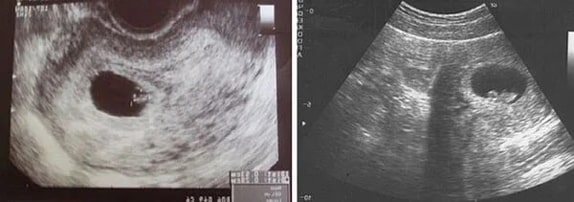

5 Haftalık Gebelik Ultrason Görüntüleri

5 haftalık gebelik bebek kilosu 5 gramdır. Bebek boyu ise henüz gelişmemiştir.

5 Haftalık İkiz Gebelik Ultrason Görüntüleri

6 Haftalık Gebelik Ultrason Görüntüleri

6 haftalık gebelik bebek boyu: 1.5 cm

6 haftalık gebelik bebek kilosu: 474 gramdır.

6 Haftalık İkiz Gebelik Ultrason Görüntüleri